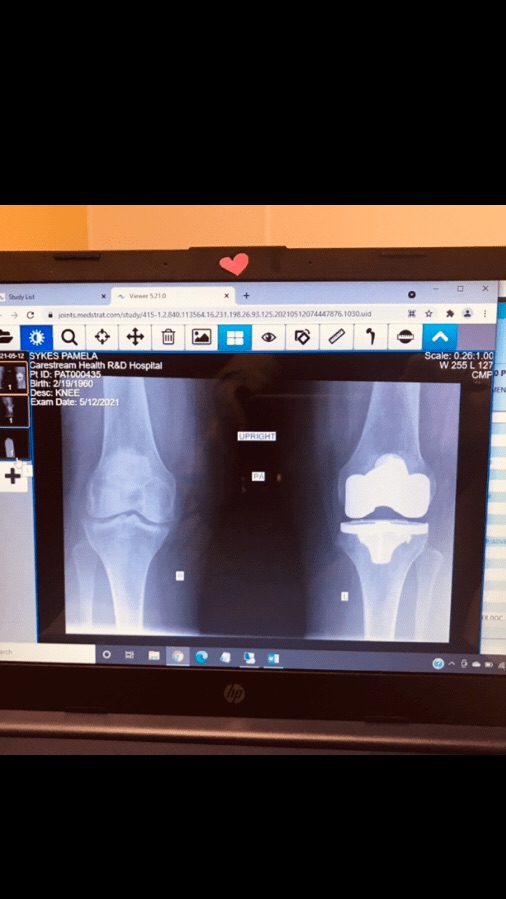

Eh, I wanted to write a post way earlier. I swear, I was dozing off in my recliner at 6:00 pm. I got a second wind around 9;00 pm. I hate that. I’m trying to wind down. I just finished drinking a mug of hot chocolate. I paid my Florida Blue (health insurance) premium. I figured since I’m getting a new knee installed on May 16th I should have it paid up.